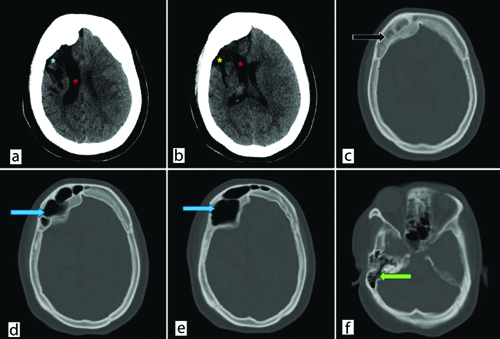

The results of blood investigations were unremarkable and within the normal range. CT imaging of the same patient showed gliotic changes with hemiatrophy of the right cerebral hemisphere and ipsilateral dilatation of the right lateral ventricle. Bony calvarial thickening was noted and hyperpneumatisation of the ipsilateral frontal sinus was observed [Table/Fig-1a-f]. These radiological and clinical indicators led to the diagnosis of DDMS.

a and b) Non Contrast Computed Tomography (NCCT) head shows right-sided gliotic and encephalomalacia changes involving frontoparietal lobe (blue asterisk) with ex-vacuo dilatation of right lateral ventricle involving frontal horn and body (red asterisks) with resultant right hemicerebral atrophy. Prominent right sylvian fissure (yellow asterisk); c) Bone window shows calvaria thickening (black arrow); d and e) Hyperpneumatisation of right frontal sinus (blue arrows); f) Hyperpneumatisation of right mastoid air cells (green arrow).